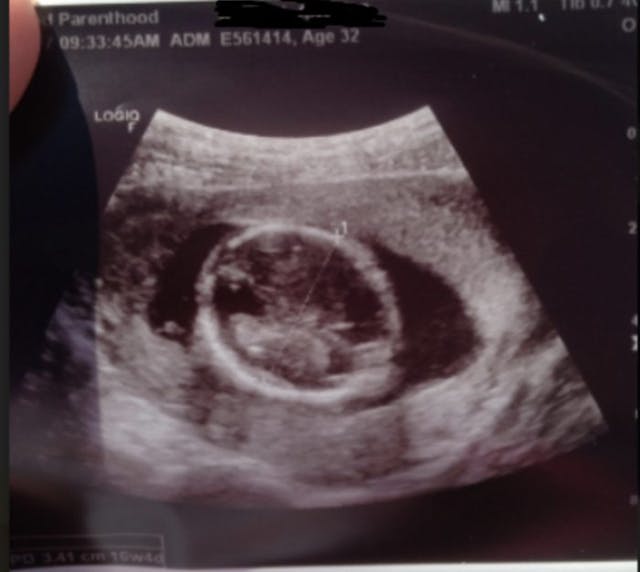

One example from 2017, as previously reported by Live Action News, was of a woman who underwent an abortion in Texas. The law at the time required Planned Parenthood to show her the ultrasound images of her baby, point out the baby’s body parts, such as arms and legs, and allow her to hear the baby’s heartbeat. But when the woman asked to see the ultrasound image, the staff showed her an image of the top of her 16-week baby’s head only — making it appear as if her baby was a mere round blob.